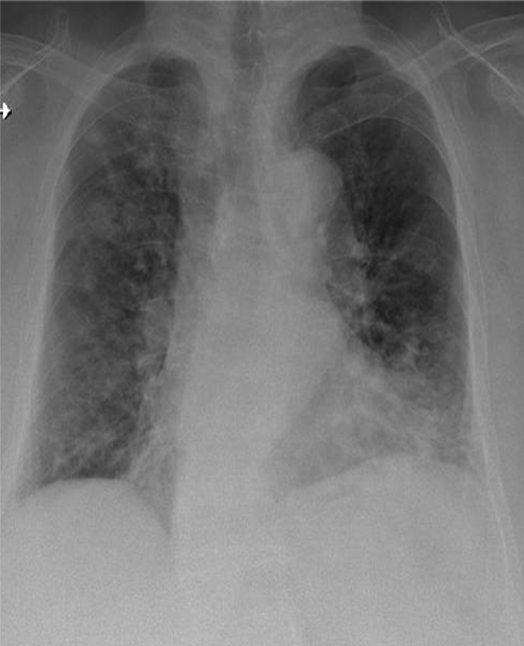

1-Thâm nhiểm phế nang dạng nốt rải rác hai phổi => VIÊM PHỔI 2-Cung động mạch chủ dãn 3-Cung động mạch chủ đóng vôi